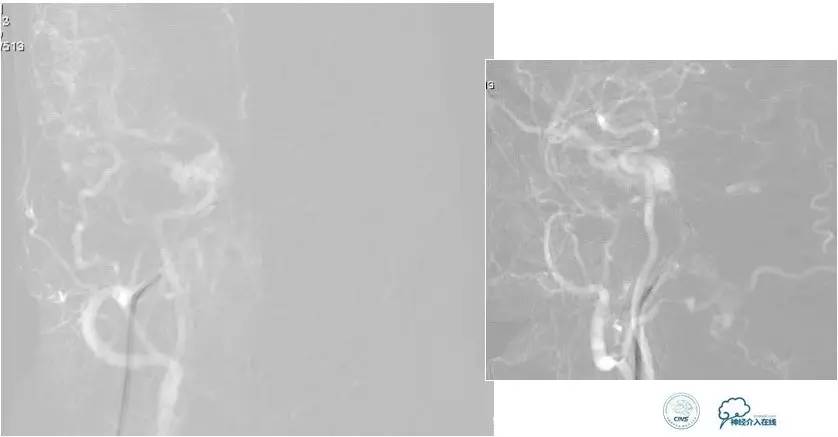

脑膜后动脉供血的小脑幕的瘘。

颈内不参与供血。

大脑后动脉有细小分支供血。

Sceptor球囊无法到达瘘口位置,放在主干内,充盈球囊后把动脉血管床内血液冲洗干净,形成楔入效果。

术后造影【Post embolization】